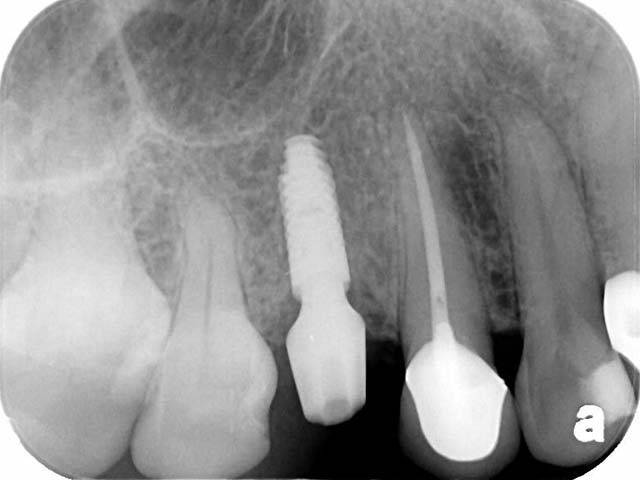

王小姐右上有一顆根管治療後的牙齒,不幸斷裂,經由電腦斷層評估,我們使用新技術,即拔即種,拔除右上第一小臼齒同時植入植體,降低患者手術疼痛感,與節省時間,經由四個月的等待牙齒終於裝置完成,回復正常咀嚼功能,與良好的美觀。